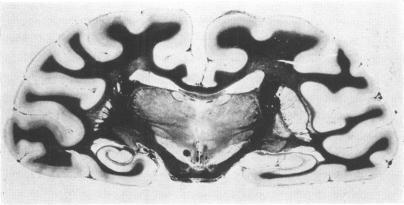

The morphological characteristics of brain death were examined in baboons and cats after artificial cerebral ischaemia. All animals showed autolytic changes in the brain, ischaemic neuronal changes, midbrain haemorrhages, focal necrosis of the brain-stem, demarcation at C 1/C 2 cord segment, and displacement of cerebellar tissue. Ultrastructural examination revealed extreme brain oedema, autolytic changes, and complete obstruction of capillaries by astrocytic and endothelial swelling and intravascular blebs. These data indicate that brain death develops in several stages. If the process starts in the supratentorial space it first leads to a breakdown of the cerebral circulation and to transtentorial herniation. As a result, midbrain haemorrhages develop and the infratentorial pressure begins to rise. The second stage is terminated by demarcation of the brain. The circulatory arrest is initially caused by venous compression but becomes irreversible when vascular obstruction develops.

在狒狒和猫身上进行人工脑缺血后,对脑死亡的形态学特征进行了检查。所有动物均表现出脑自溶变化、缺血性神经元变化、中脑出血、脑干局灶性坏死、C1/C2脊髓节段分界以及小脑组织移位。超微结构检查显示极度脑水肿、自溶变化,以及星形细胞和内皮细胞肿胀及血管内气泡导致毛细血管完全阻塞。这些数据表明脑死亡分几个阶段发展。如果该过程始于幕上空间,首先会导致脑循环中断和经天幕疝形成。结果,中脑出血发生,幕下压力开始升高。第二阶段以脑分界结束。循环停止最初是由静脉受压引起的,但当血管阻塞发生时就会变得不可逆转。